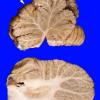

NORMAL

Normal Adult Brain - Coronal and Axial (2)